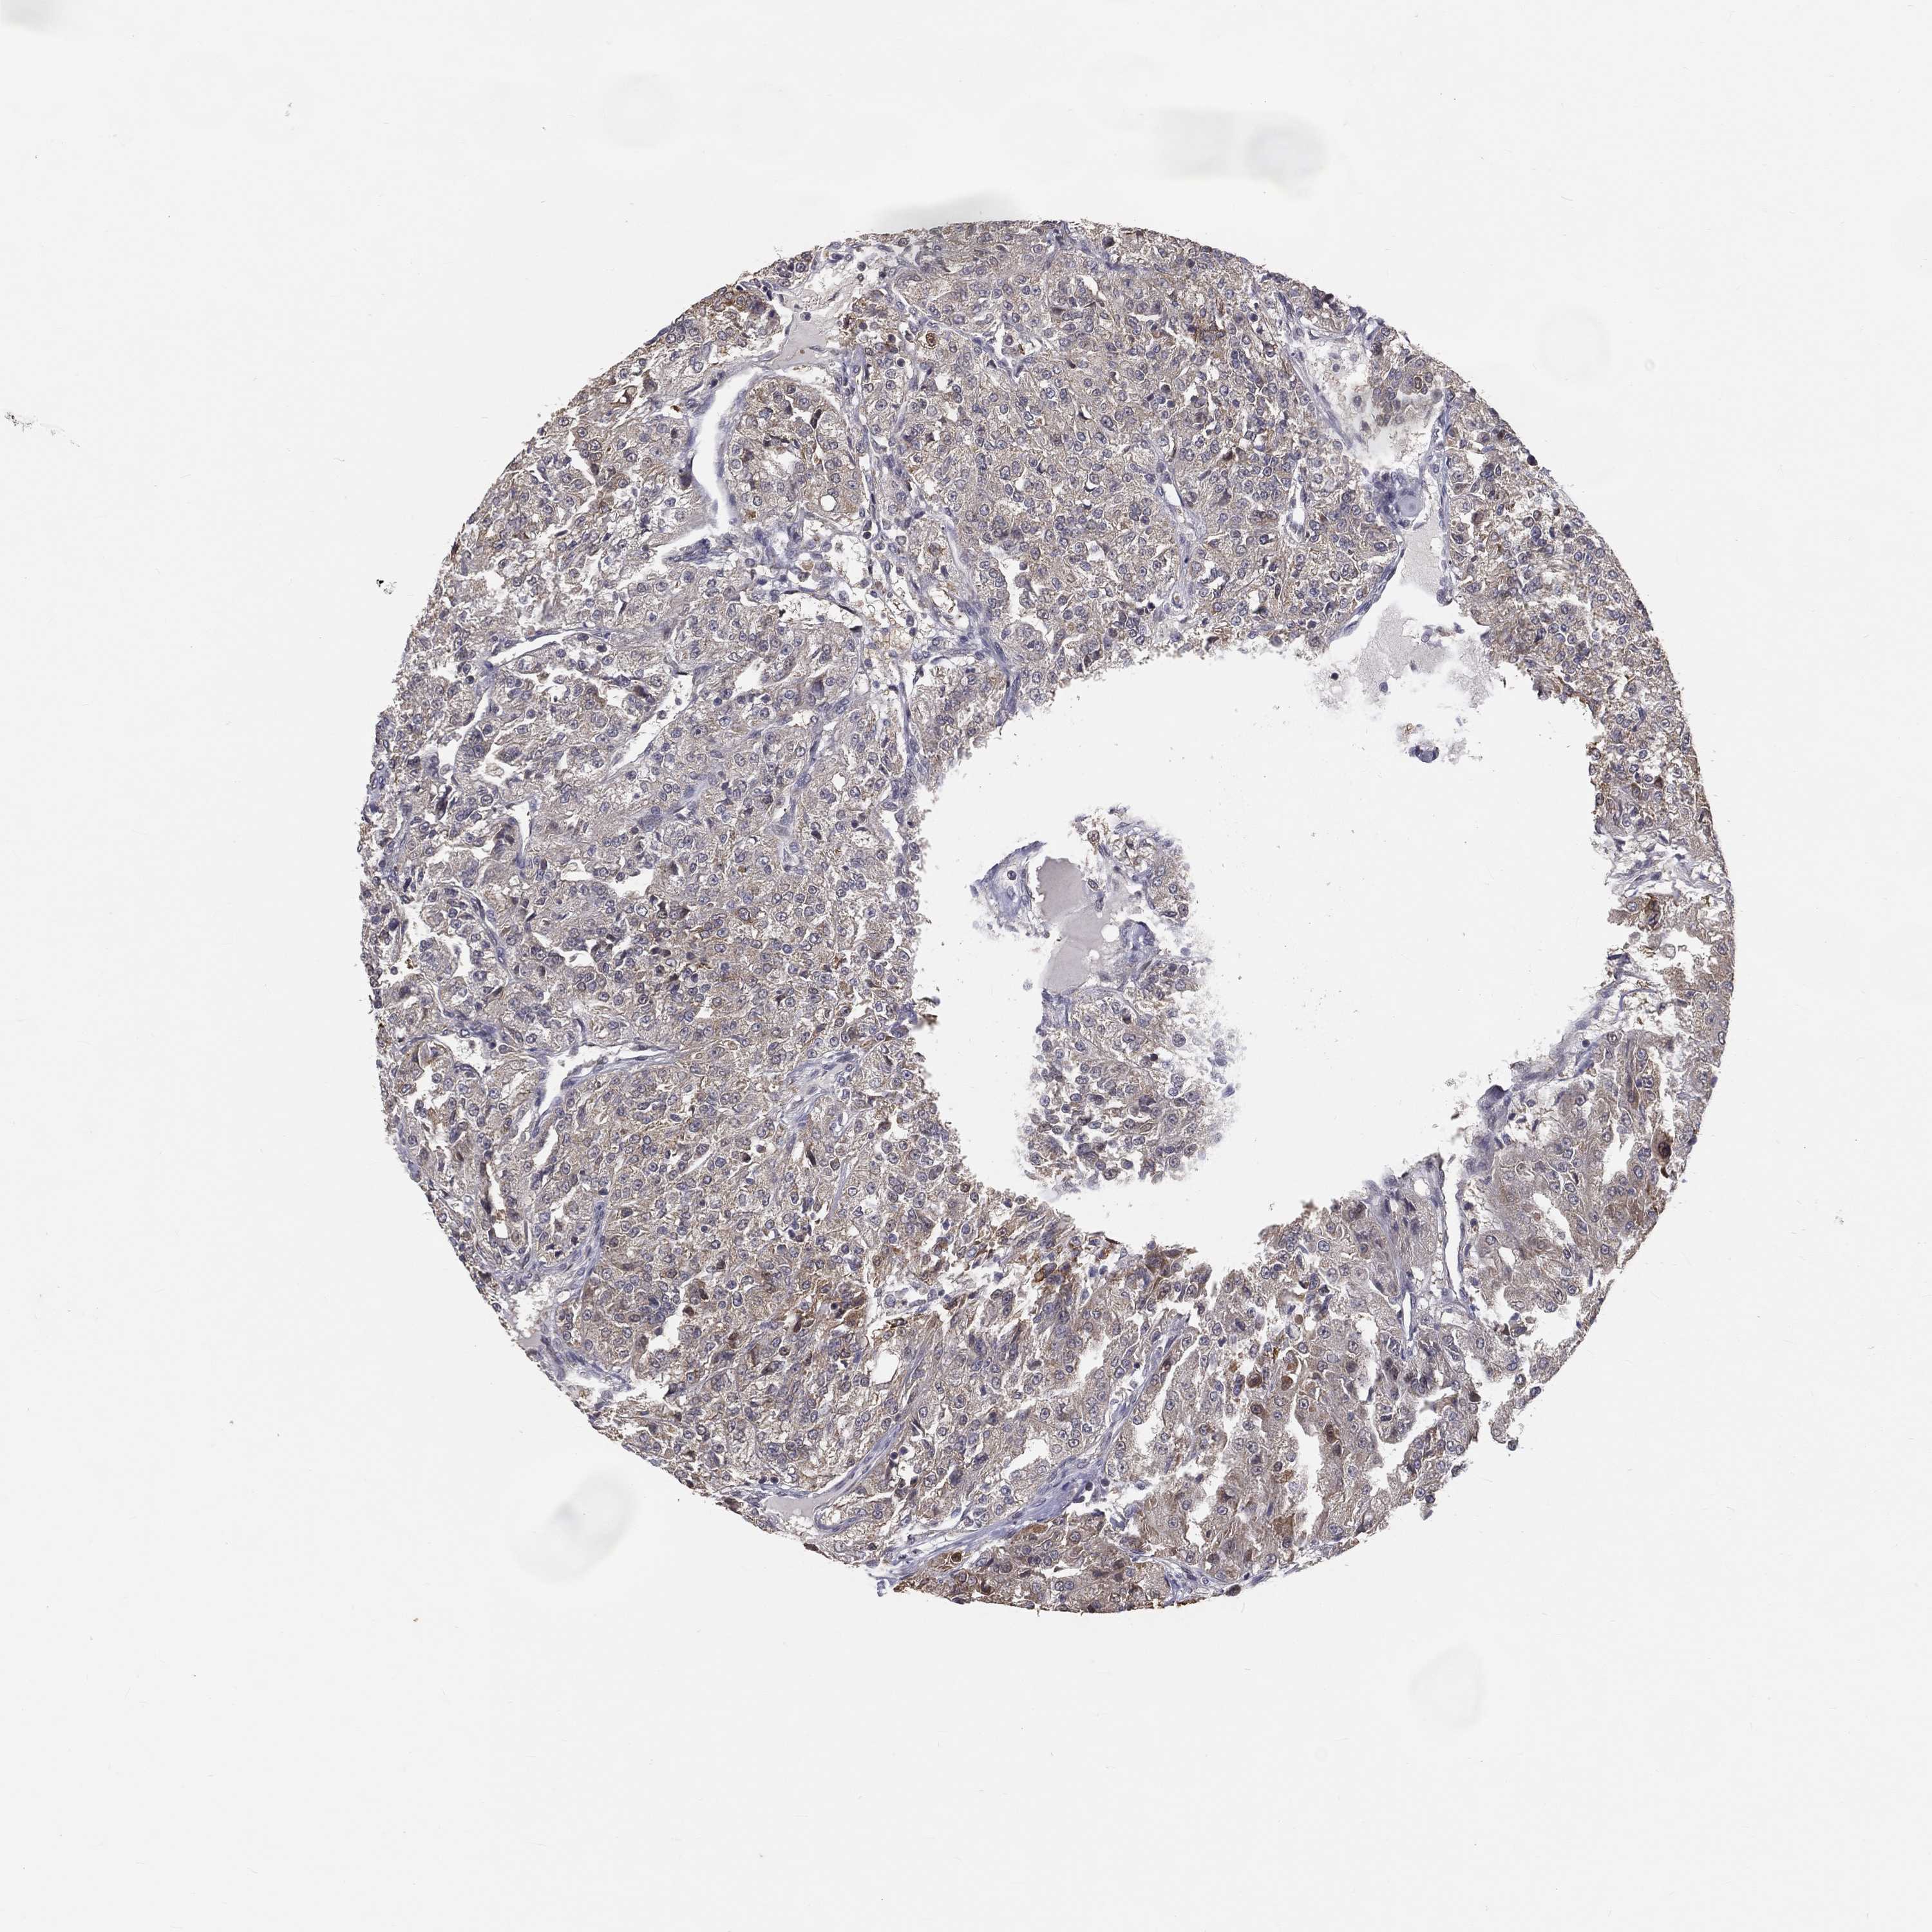

KIDNEY RENAL PAPILLARY CELL CARCINOMA (TCGA) - Interactive survival scatter ploti

The Survival Scatter plot shows the clinical status (i.e. dead or alive) for all individuals in the patient cohort, based on the same data that underlies the corresponding Kaplan-Meier plots. Patients that are alive at last time for follow-up are shown in blue and patients who have died during the study are shown in red.

The x-axis shows the expression levels (FPKM) of the investigated gene in the tumor tissue at the time of diagnosis. The y-axis shows the follow-up time after diagnosis (years). Both axes are complimented with kernel density curves demonstrating the data density over the axes. The top density plot shows the expression levels (FPKM) distribution among dead (red) and alive patients (blue). The right density plot shows the data density of the survived years of dead patients with high and low expression levels respectively, stratified using the cutoff indicated by the vertical dashed line through the Survival Scatter plot. This cutoff is automatically defined based on the FPKM cutoff that minimizes the p-score. The cutoff can be changed by dragging the vertical line or by entering a cutoff value in the square labeled "Current cut-off".

Under the Survival Scatter plot the p-score landscape (black curve; left axis) is shown together with dead median separation (red curve; right axis). Dead median separation is the difference in median mRNA expression between patients who have died with high and low expression, respectively. It is calculated as follows: median FPKM expression of dead patients with high expression - median FPKM expression of dead patients with low expression. This is intended to aid the user in visually exploring custom cutoffs and the associated p-scores and dead median separation.

Individual patient data is displayed and can be filtered by clicking on one or more of the category buttons on the top of the page. Categories describing expression level and patient information include: high, low, alive, dead, female, male and tumor stages. The scale of the x-axis can be toggled between linear and log-scale by clicking on the "x log" button. Mouse-over function shows TCGA ID, patient information and mRNA expression (FPKM) for each patient.

& Survival analysisi

Kaplan-Meier plots summarize results from analysis of correlation between mRNA expression level and patient survival. Patients were divided based on level of expression into one of the two groups "low" (under cut off) or "high" (over cut off). X-axis shows time for survival (years) and y-axis shows the probability of survival, where 1.0 corresponds to 100 percent.

MRPL46 is not prognostic in Kidney Renal Papillary Cell Carcinoma (TCGA)